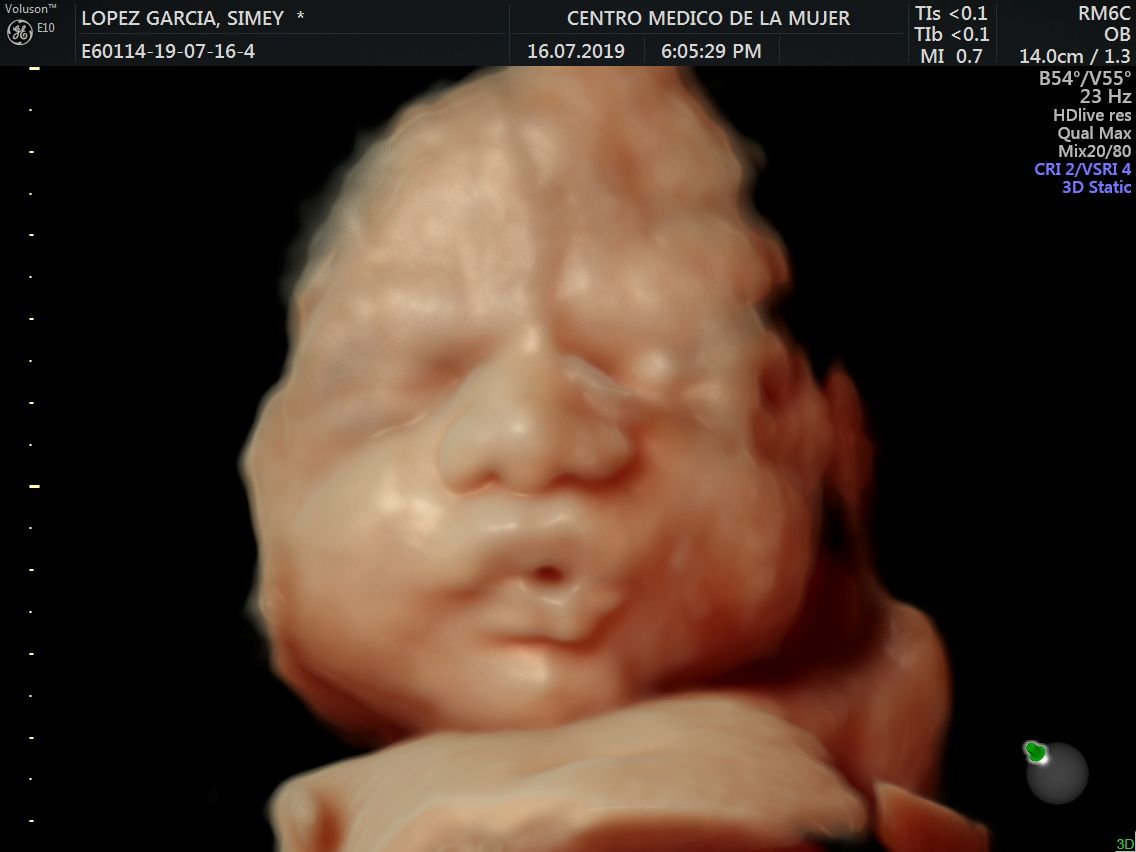

Fotos y videos

ECO Anatómico

Consiste en la evaluación especifica de cada organo y sistema del bebé con medidas detalladas de cada parte para evaluar su crecimiento proporcional.